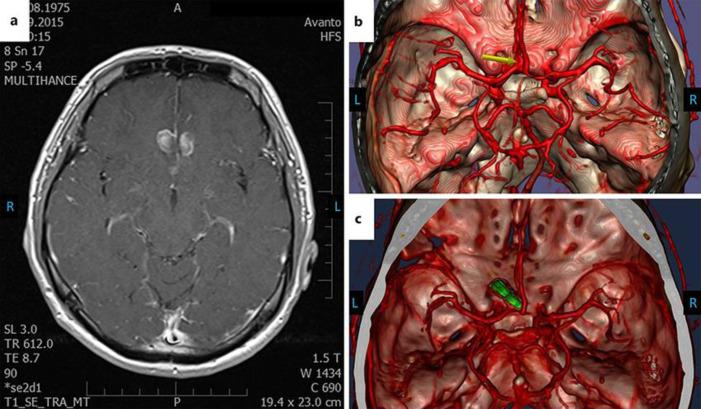

The misdiagnosis of a ruptured aneurysm directly endangers patient's life and health due to the high risk of rebleeding and its sequelae. In this paper, we present two uncommon cases of anterior communicating artery aneurysm rupture with a relatively small intracerebral bleeding, seemingly without a diffuse subarachnoid hemorrhage (SAH), and a relatively mild clinical presentation. In these cases, the initial diagnosis failed, leading to missed aneurysmal ruptures. The atypical or mild clinical presentation, and the absence of SAH on computed tomography (CT) and/or magnetic resonance imaging (MRI) scan or absent blood in the cerebrospinal fluid (CSF) are all factors which could lead to a false or delayed diagnosis. Meticulous evaluation of patient's symptoms, CT, MRI scans, and CSF findings are mandatory. The possibility of a small blood clot without a diffuse SAH must be considered.

由于再出血风险及其后遗症的危险性高,动脉瘤破裂的误诊会直接危及患者的生命和健康。在本文中,我们呈现了两例罕见的前交通动脉瘤破裂病例,其脑内出血相对较少,看似没有弥漫性蛛网膜下腔出血(SAH),临床表现相对较轻。在这些病例中,最初的诊断出现失误,导致动脉瘤破裂被漏诊。非典型或轻微的临床表现,以及计算机断层扫描(CT)和/或磁共振成像(MRI)扫描未显示SAH或脑脊液(CSF)中无血液,都是可能导致误诊或诊断延迟的因素。必须对患者的症状、CT、MRI扫描及CSF检查结果进行细致评估。必须考虑存在无弥漫性SAH的小血凝块的可能性。